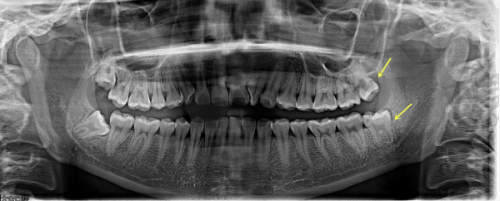

1. **精良的设备**:医院引进了一系列精良的口腔医疗设备,如数字化口腔全景机、口腔 CT、隐形矫正设计系统等。这些设备能够为医生提供正确的诊断依据,提高治疗的精细度和成效。例如,数字化口腔全景机可以快速、清晰地拍摄口腔全景图像,帮助医生全方面了解患者的口腔状况;口腔 CT 则能够提供三维立体的图像,为种植手术等复杂治疗提供更加详细的信息。